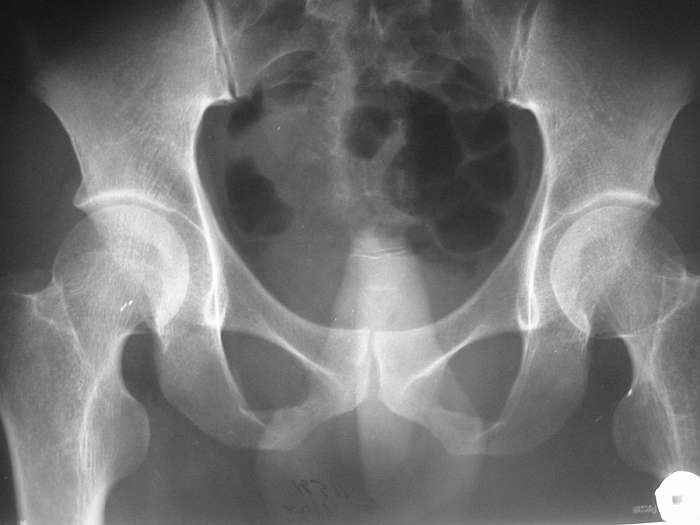

P.S. хотелось бы увидеть снимок таза

СА> P.S. хотелось бы увидеть снимок таза

Сегодня забегался и забыл про снимок, sorry. Завтра выложу.

Сегодня пациент мочится самостоятельно. Консультирован неврологом. Неврологического дефицита не найдено. Сила в конечностях сохранена, снижена слева в нижней конечности из-за болей в паховой области. В свете последних решений "партии и правительства", будем накладывать реклинирующий корсет и готовить к "отплытию". Грустно, так как этот, совсем не соотечественник, стал мне глубоко симпатичен: очень мужественный молодой человек.

ЗЫ: В приложении снимок таза.